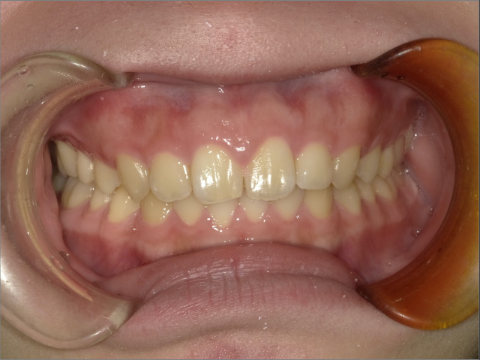

ご年齢 35歳男性 治療期間 2022/08/22〜2023/03/24(1年5ヶ月)

診断 110,000円(税込) アライナー 550,000円(税込) リテーナー 55,000円(税込)

ご年齢 35歳男性

治療期間 2022/08/22〜2023/03/24(1年5ヶ月)

診断 110,000円(税込)

アライナー 550,000円(税込)

リテーナー 55,000円(税込)

BEFORE

AFTER